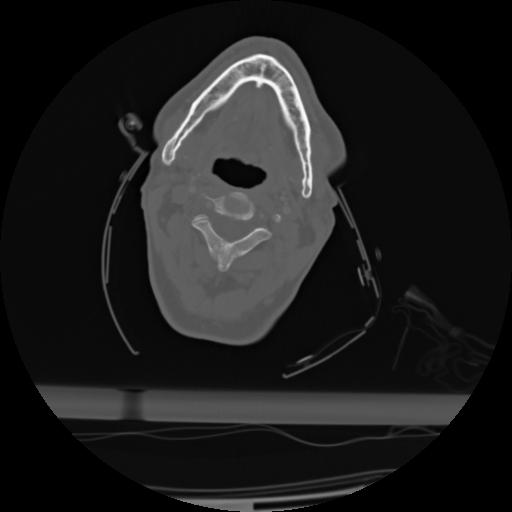

21 ANGIO,CE,Axial,3.0,ANGIO,,